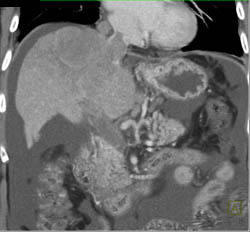

Hepatoma